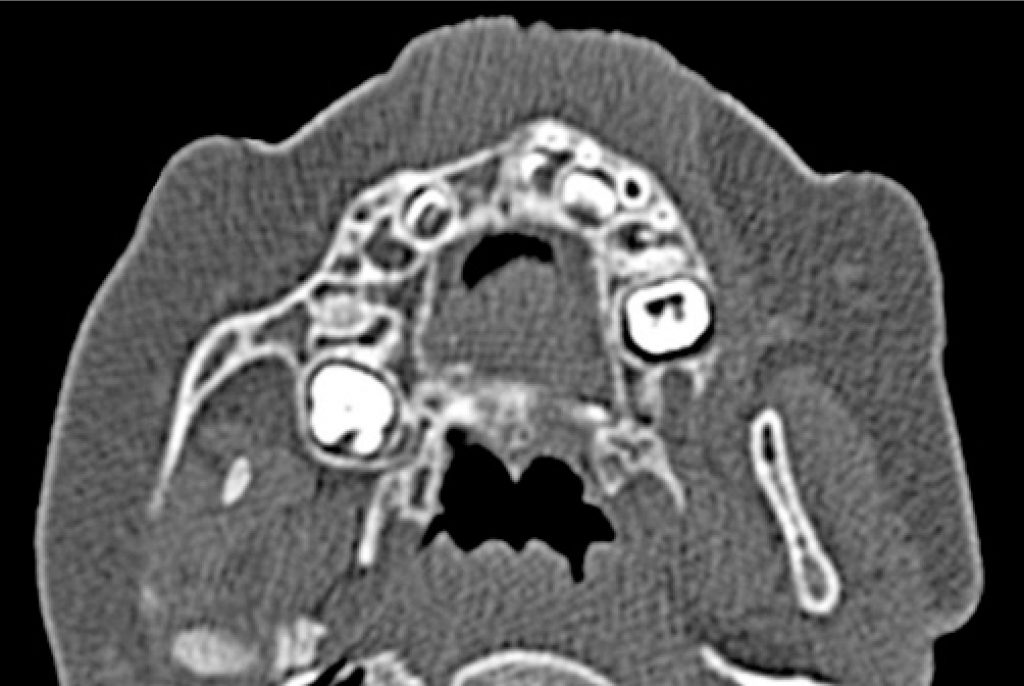

O tumor neuroectodérmico melanocítico da infância é uma neoplasia rara e de crescimento rápido. Neste estudo, relata-se o caso de uma paciente do sexo feminino de 6 meses de idade, que apresentou tumefação na região anterior de maxila. A reconstrução tomográfica revelou área unilocular hipodensa e expansiva associada ao incisivo central superior direito decíduo. Realizou-se biópsia incisional, considerando as hipóteses diagnósticas de cisto dentígero, tumor odontogênico adenomatoide, tumor neuroectodérmico melanocítico da infância e rabdomiossarcoma. Microscopicamente, a lesão revelou população celular bifásica, consistindo de células pequenas, ovoides, de aparência neuroblástica, e de células epitelioides, contendo melanina. A análise imuno-histoquímica demonstrou que o componente celular contendo melanina era positivo de forma intensa e difusa para HMB-45 e Melan-A, mas levemente positivo para S100. Com base nestes achados, foi estabelecido o diagnóstico definitivo de tumor neuroectodérmico melanocítico da infância. Em seguida, foi realizada a enucleação da lesão com curetagem cuidadosa. Após 2 anos de acompanhamento, não foram verificadas evidências clínicas ou radiográficas de recorrência. O presente caso destaca a importância do diagnóstico precoce e da intervenção terapêutica no momento apropriado, a fim de alcançar um desfecho favorável para o paciente.